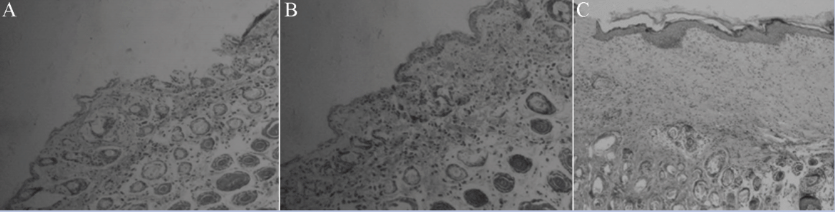

Full-thickness skin wounds, histological examination. After 2 weeks, the wounds in group C had almost completely healed. In group A, the wounds were partially covered with granulation tissue and ingrowth of fibroblasts had formed granulation tissue (Figure 5A). In wounds treated with hUCMSCs combined with the collagen membrane or the collagen-fibrin double-layered membrane (group B and C), a good combination between the treatment material and wound edge was formed. The basal layer, stratum spinosum, stratum granulosum, stratum lucidum, and stratum corneum could clearly be observed. In group C, the reepithelialization process was rapid. Collagen was evenly distributed under the neonatal keratinocytes. The basal layer was flat and closely combined with the collagen, and formation of epithelization was observed by histological examination (Figures 5B and 5C).

Figure 5. Histologic findings of skin tissue. (A) Control group (group A); (B) human umbilical cord mesenchymal stem cells(HUCMSCs) combined with collagen membrane treated group (group B); (C) HUCMSCs combined with collagen-fibrin doublelayer membrane treated group (group C).